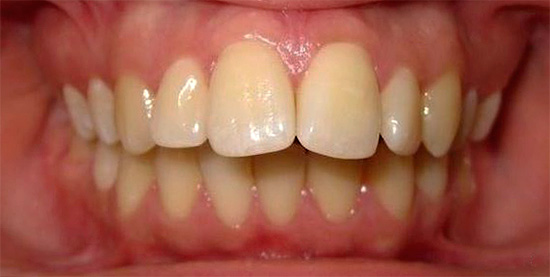

Nota come la forma della mascella cambia dopo il trattamento per un morso distale:

Morso mesiale

Rispetto al morso distale, la situazione opposta si osserva con il morso mesiale - quando la mascella superiore è di dimensioni inferiori rispetto alla mascella inferiore. Questa è la terza classe di malocclusione secondo la classificazione di Engle.